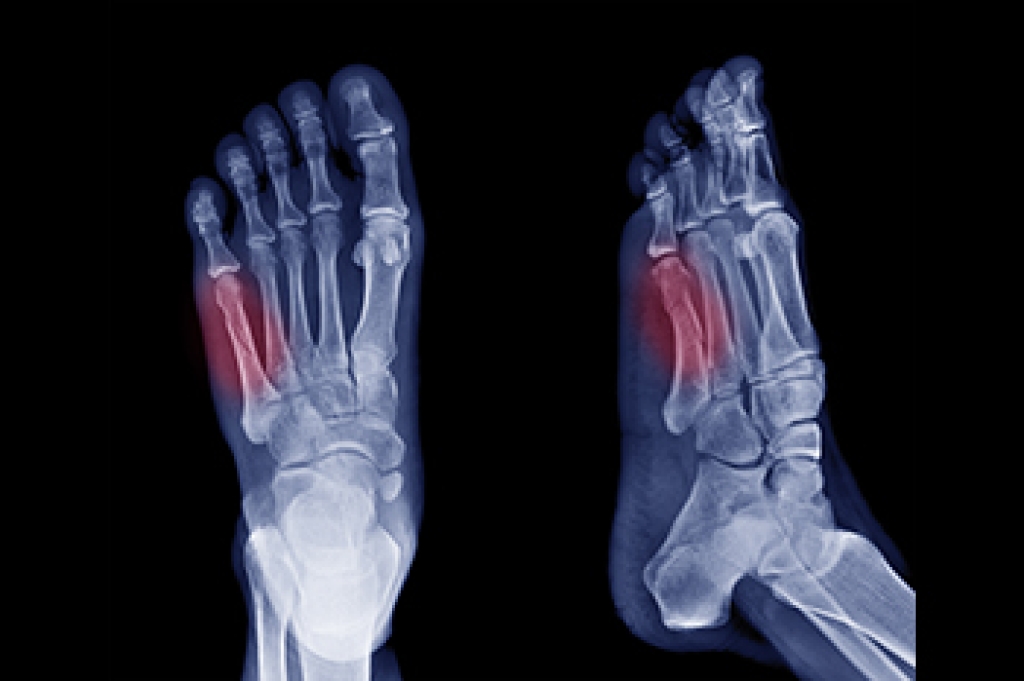

Fractures of the fifth metatarsal occur in various forms, depending on the location and cause of the break. The fifth metatarsal is a long bone located on the outer edge of the foot, connecting the midfoot to the base of the pinky toe. It plays an important role in maintaining balance, supporting weight, and enabling movement during activities such as walking, running, and jumping. Avulsion fractures, the most frequent type, happen when a tendon pulls a small piece of bone off the base of the fifth metatarsal. Dancer’s fractures, caused by twisting injuries, involve a diagonal break along the bone’s shaft. Stress fractures, resulting from repetitive activities like running, develop gradually and often affect the shaft or neck. Head and neck fractures of the 5th metatarsal typically occur from direct trauma to the bone. A podiatrist can use imaging tests to determine the type of fracture you have sustained. For guidance with a fractured foot bone, it is suggested that you schedule an appointment with a podiatrist for a diagnosis and treatment options.

A broken foot requires immediate medical attention and treatment. If you need your feet checked, contact Frederick Matthews, DPM from Innovative Foot and Ankle Care. Our doctor can provide the care you need to keep you pain-free and on your feet.

Broken Foot Causes, Symptoms, and Treatment

A broken foot is caused by one of the bones in the foot typically breaking when bended, crushed, or stretched beyond its natural capabilities. Usually the location of the fracture indicates how the break occurred, whether it was through an object, fall, or any other type of injury.

Those that suspect they have a broken foot shoot seek urgent medical attention where a medical professional could diagnose the severity.

Treatment for broken bones varies depending on the cause, severity and location. Some will require the use of splints, casts or crutches while others could even involve surgery to repair the broken bones. Personal care includes the use of ice and keeping the foot stabilized and elevated.